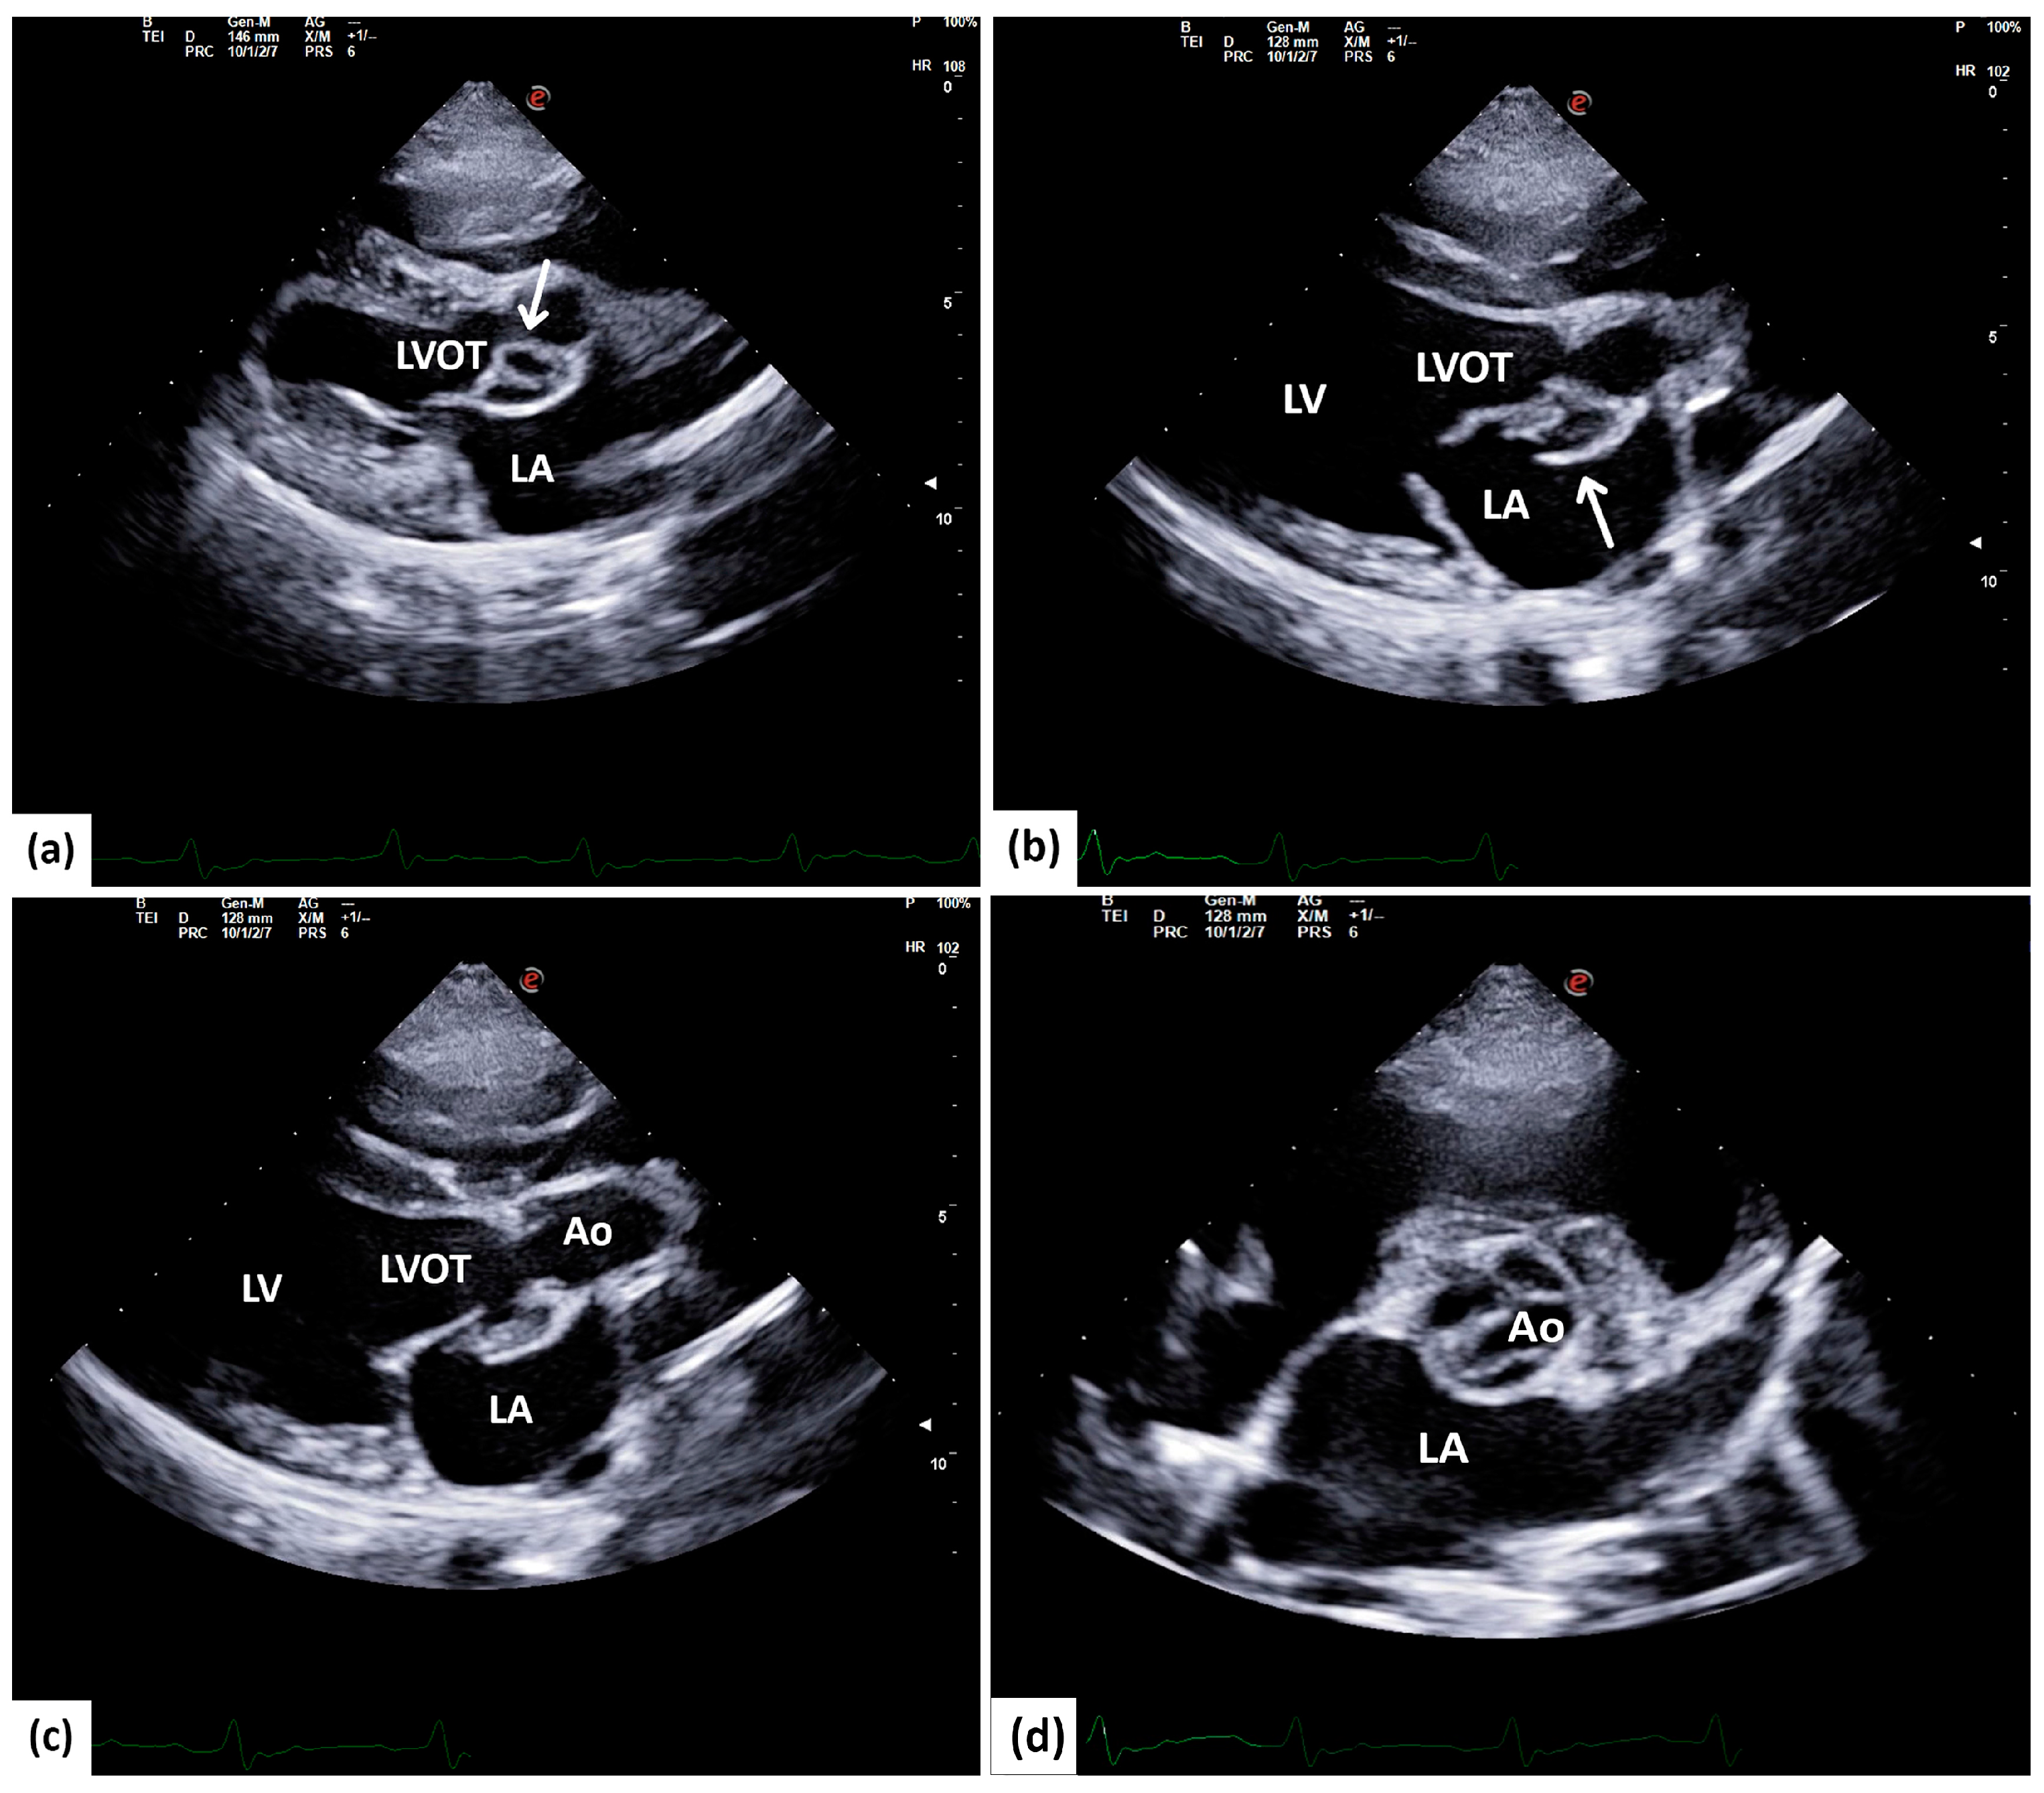

The right chambers of the heart showed no remarkable changes. The investigation of the aortic valves and trunk showed notable changes in the aortic cusps. Immediately under the non-coronary aortic cusp, isoechoic visible oscillating irregular-shaped growths were seen attached to the mitral–aortic intervalvular wall, which outline a rounded, double-cavitary “aneurysmal-like” structure (Figure 1a, Video S1) that resembles a paravalvular abscess. The mitral–aortic wall shows a discontinuation, at the level of which the isoechoic structures previously described are seen bulging into the left atrium (LA) (Figure 1b,c; Video S3). In the short-axis view at the base of the heart, the changes are confirmed to be affecting the non-coronary aortic cusp, where cavitary changes are obviously seen (Figure 1d).

Figure 1. A five-chamber long-axis view in a 7.7-year-old American Staffordshire mix male. (a) A double-cavitary structure with isoechoic walls is identified at the level of the left ventricle outflow tract (arrow). (b,c) Discontinuation of the aortomitral intervalvular wall (arrow) with an isoechoic structure protrusion through the discontinuation into the left atrium (LA). (d) A short-axis view at the base of the heart shows cavitary changes on the non-coronary aortic cusp. LVOT = left ventricle outflow tract, LA = left atrium, LV = left ventricle, AO = aorta.